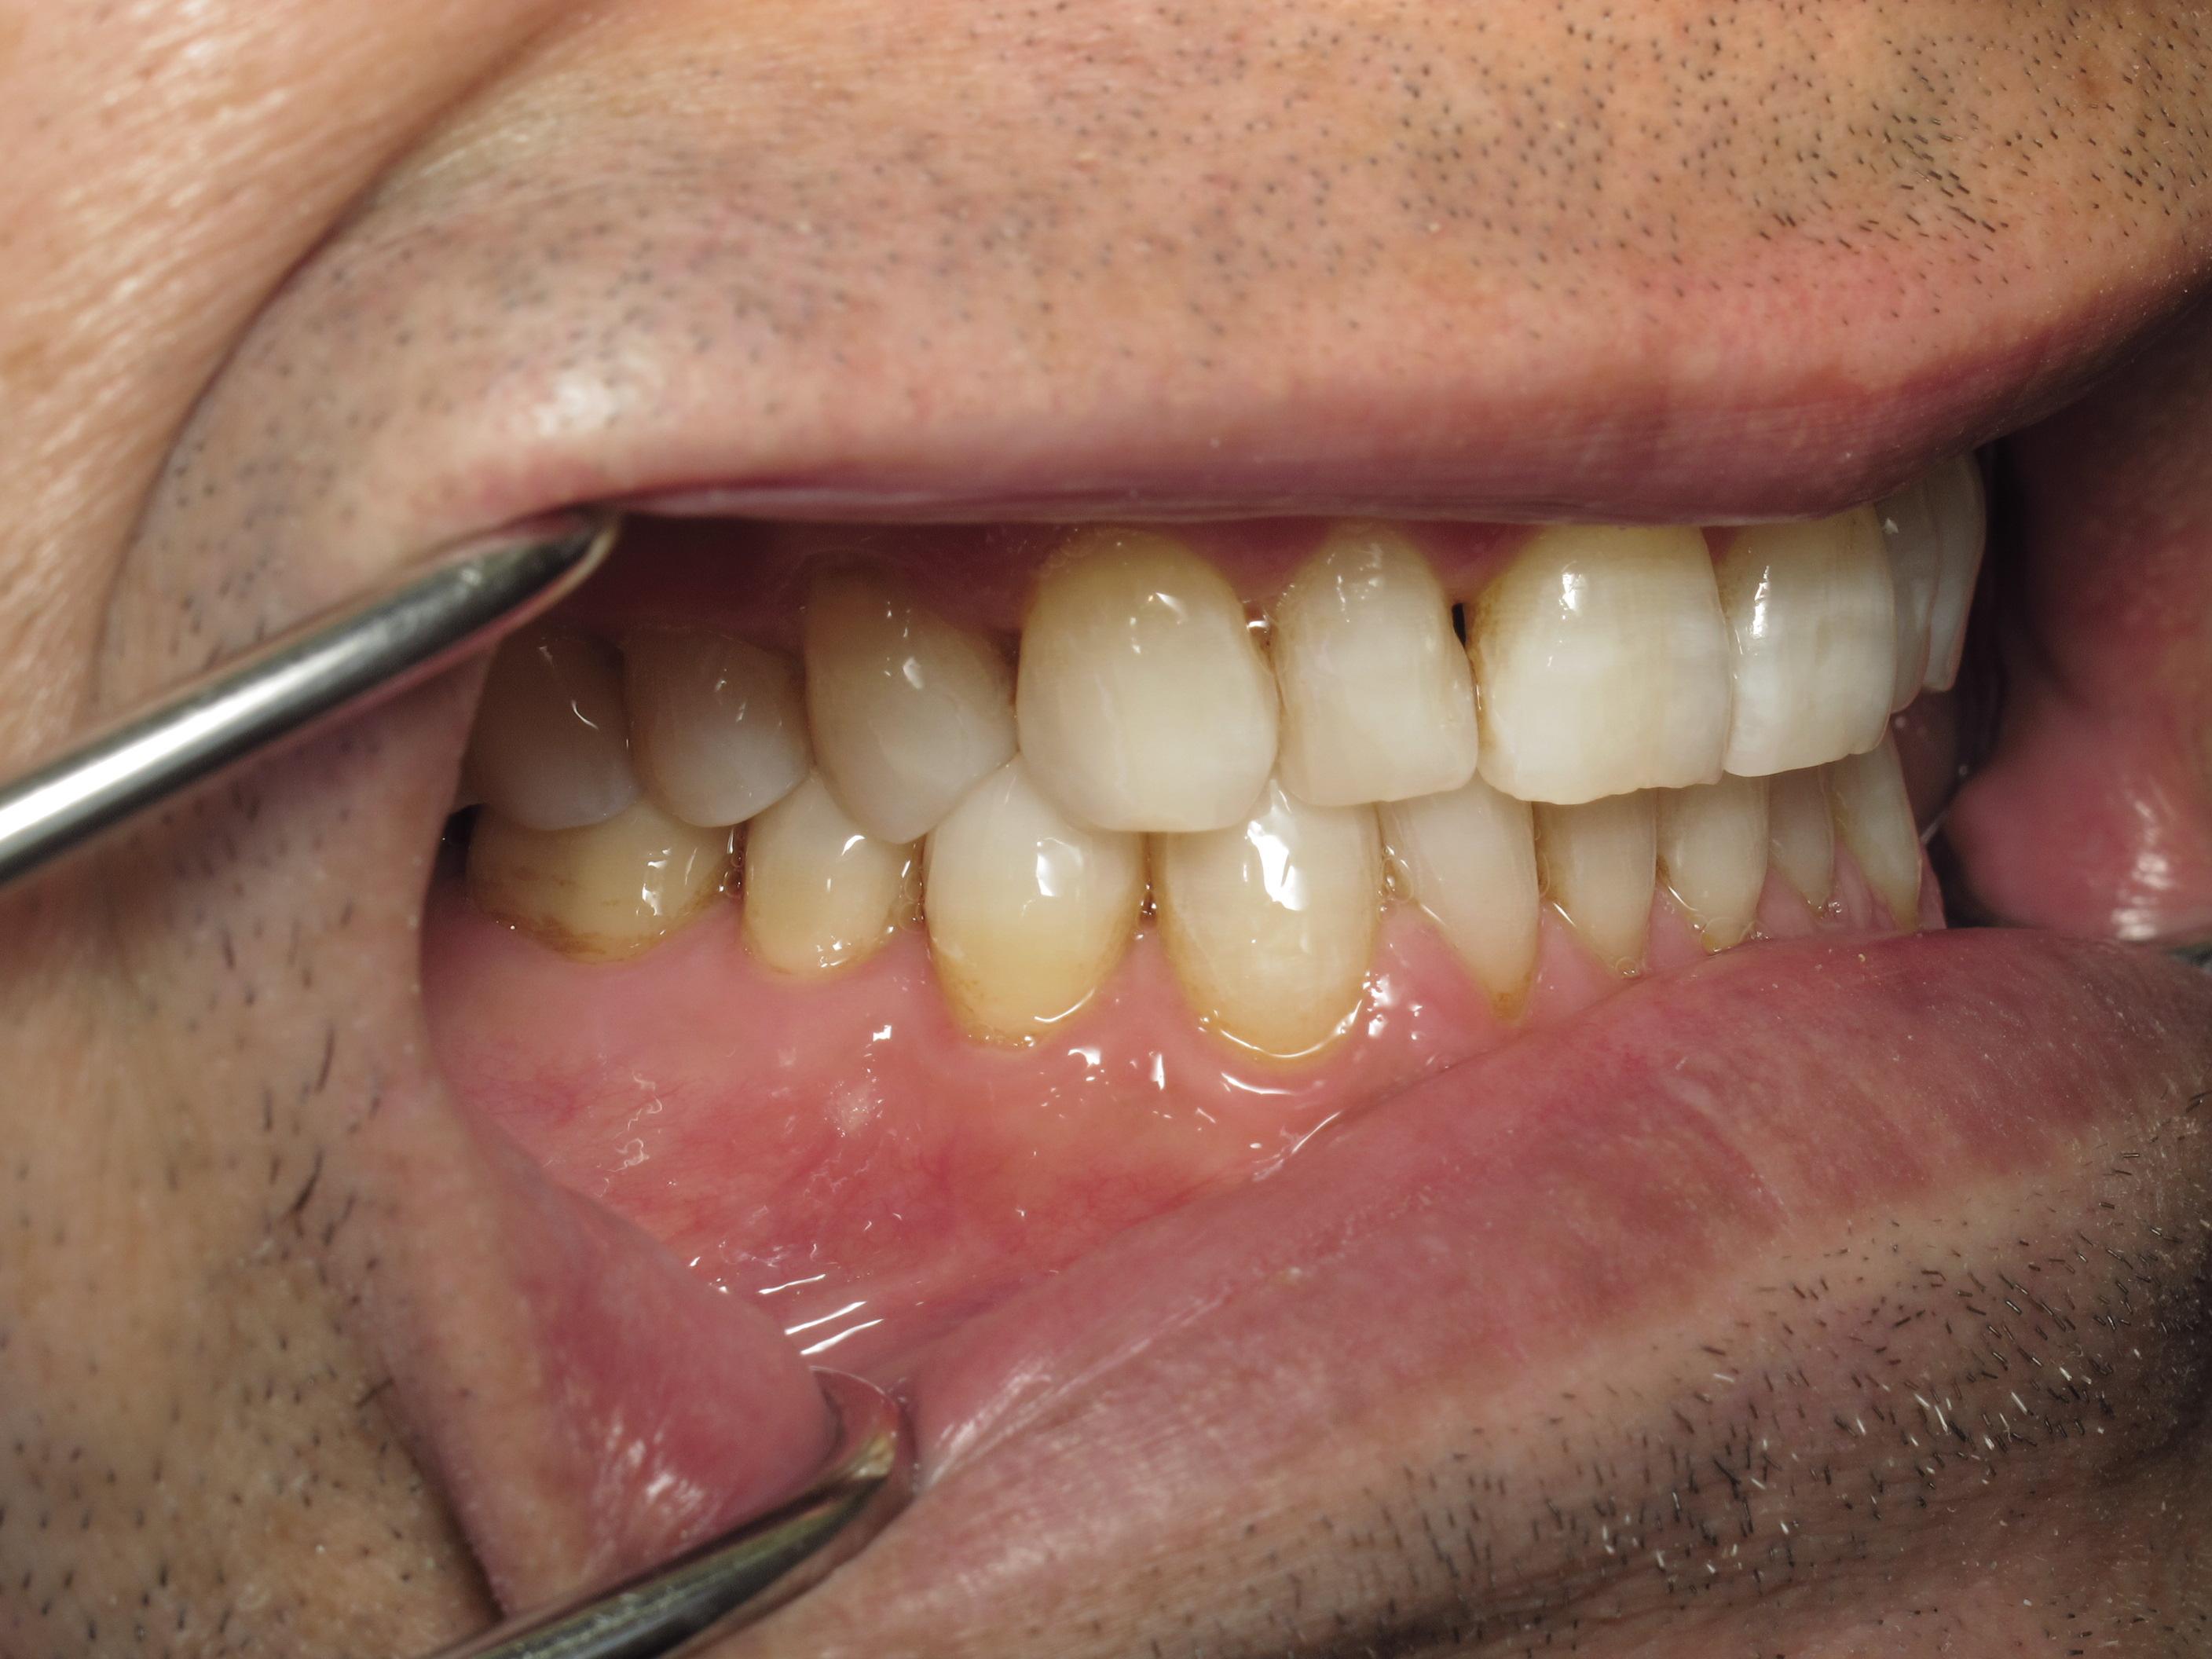

https://demo.discussdentistry.com/forums/topic/accident-victim-upper-arch-rehab/#post-26049 <![CDATA[Accident victim => Upper arch rehab]]> https://demo.discussdentistry.com/forums/topic/accident-victim-upper-arch-rehab/#post-26049 Tue, 30 Apr 2024 04:28:51 +0000 Amit Kumar The patient presents after falling in the bathroom and hitting his face on the countertop.  Previously, he had a PFM crown in the upper anterior.  He needed root canal therapy.

The patient is a stage performer (actor) and has appeared in some minor film roles, so he wanted to restore his teeth so that his smile would appear “white” on camera.

The patient’s lower teeth need attention and we will start the process once the patient’s finances have improved.

eMax material was used.  Pics were taken immediately after cementation.Before LeftBefore FrontBefore RightAfter FrontAfter LeftAfter Right